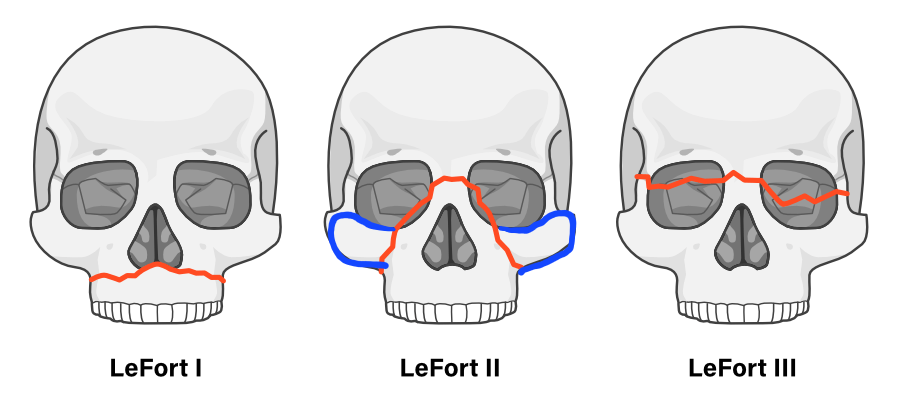

Notice the blue part added in the lf2 diagram.

Instead of doing the big lefort 3 cut, why cant we just add the cheekbone part to the lefort 2?

Instead of doing the big lefort 3 cut, why cant we just add the cheekbone part to the lefort 2?